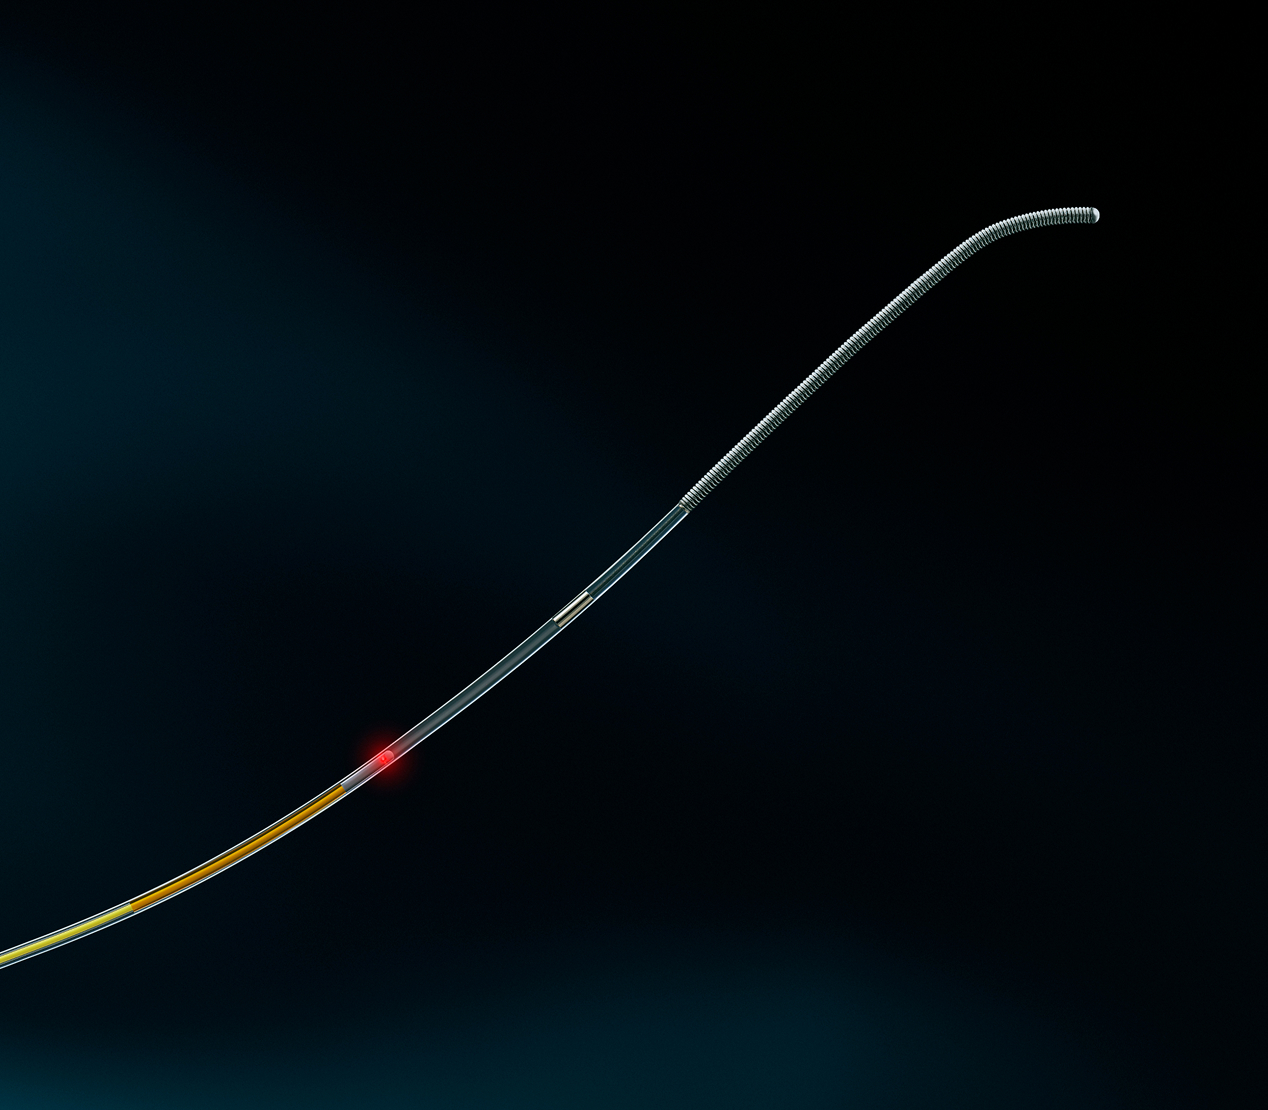

Designed to navigate the highly tortuous neurovascular anatomy

Using standard neurovascular workflow, the Spryte nOCT imaging probe brings a micro-optical fiber into the brain’s arteries, allowing for imaging from the inside out. The imaging platform includes an AI-powered console, an optical module, and a fiber-optic, neuroendovascular probe specifically designed to navigate the small, tortuous vasculature of the brain.